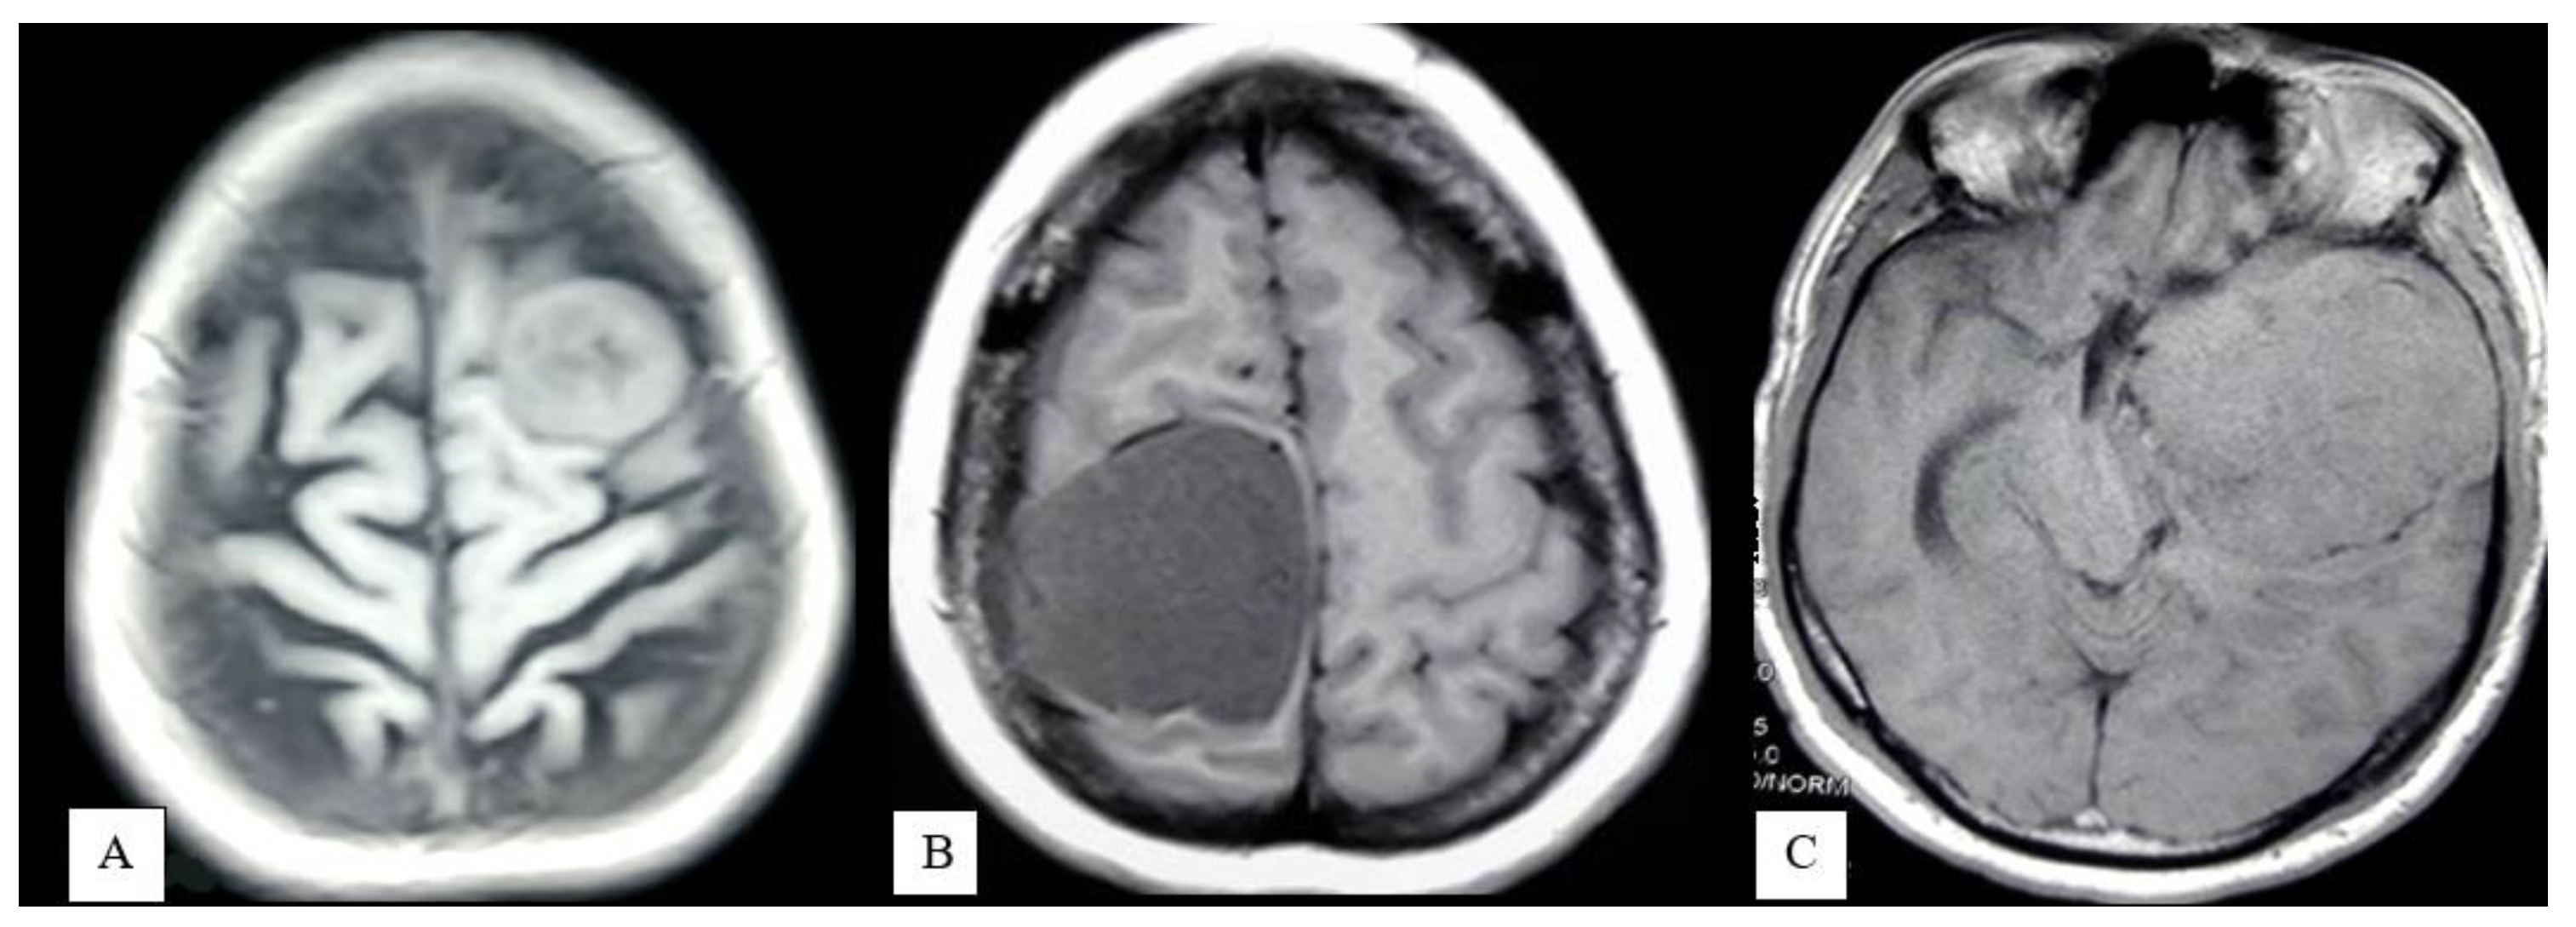

- Extrapial: Surgical cleavage plane lies outside the pia mater in more than two-thirds of the overall interface between tumor and cortex, regardless of whether an arachnoid membrane could be clearly identified (Figure 4A);

- Mixed: Cleavage plane lies outside the pia mater in more than one-third but less than two-thirds of overall interface (Figure 4B);

- Subpial: Tumor capsule exceeds the pia mater in more than two-thirds of the tumor cortex interface, and the surgeon was required to pass underneath the pia mater because of its incorporation into the tumor capsule (Figure 4C).